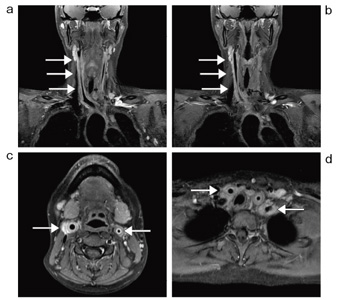

図5 IDEALを用いた造影後T1強調像(1.5T)

a,b:冠状断像 c,d:横断像

CHESS法などでは不可能であった複雑な形状や空気と接するような領域においても,均一な脂肪抑制効果が得られ,炎症を起こしている動脈壁の肥厚と異常増強効果が明瞭に観察できる。

(画像ご提供:東京大学医学部附属病院様)